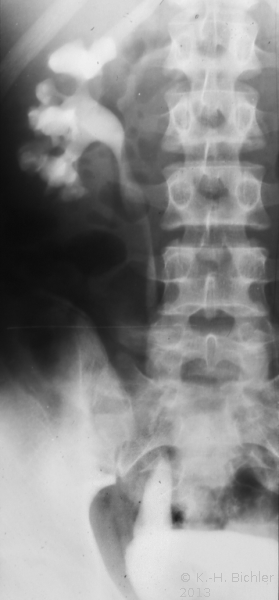

Bei dem 11 Jahre alten Mädchen mit Ureterozele und partiellem sekundärem Megaureter wurde wegen rezidivierender Harnwegsinfekte (Pyelonephritis) die Ureterozelenabtragung und Reimplantation durchgeführt und zwar mit Rücksicht auf das Lebensalter und um bei der vorgeschädigten linken Niere einen bei alleiniger Schlitzung drohenden Reflux zu verhindern (Abbildung 8).